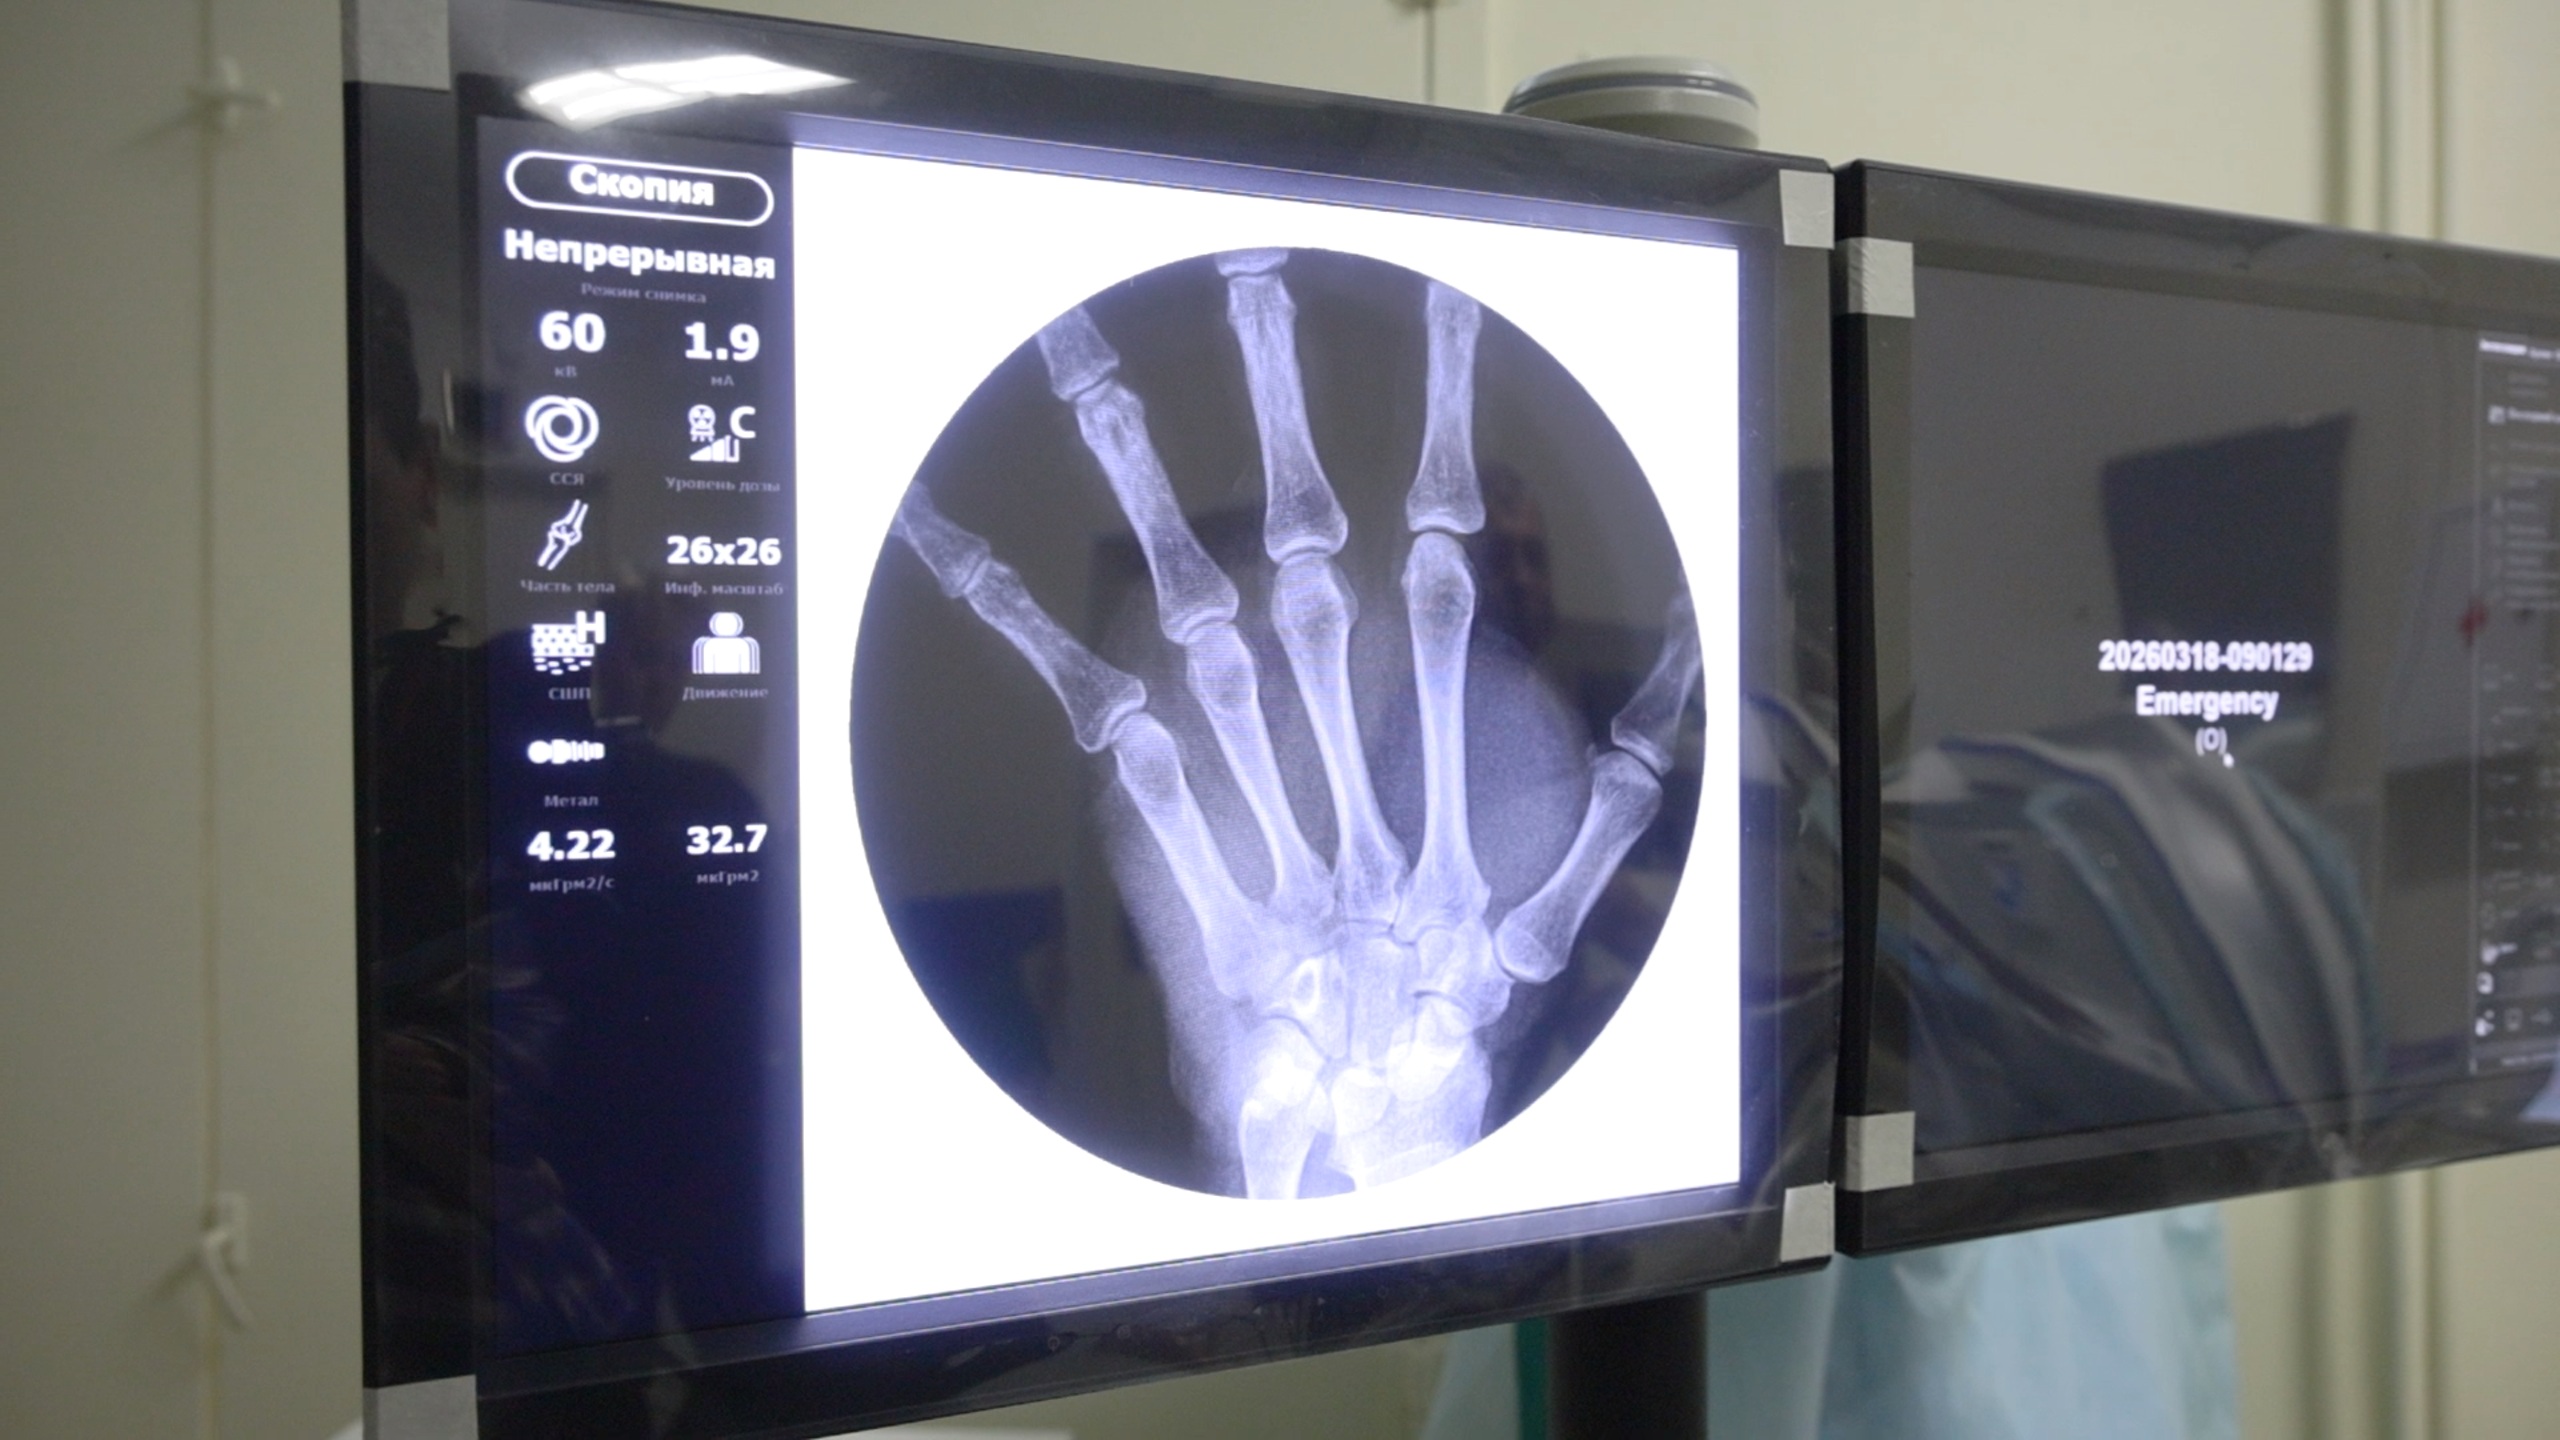

В Петропавловск-Камчатскую городскую больницу №2 поступил современный передвижной рентгенохирургический аппарат типа «С-дуга». Оборудование стоимостью около 20 миллионов рублей было закуплено по распоряжению губернатора Владимира Солодова.

По распоряжению губернатора Камчатского края Владимира Солодова в травматологическое отделение Петропавловск-Камчатской городской больницы №2 поступил современный передвижной рентгенохирургический аппарат типа «С-дуга». Стоимость высокотехнологичного оборудования составила около 20 миллионов рублей. Приобретение соответствует задаче по повышению качества и доступности медицинской помощи, поставленной президентом России Владимиром Путиным.

Аппарат «С-дуга» представляет собой передвижную рентгенохирургическую систему, название которой связано с С-образной формой штатива. Его ключевые особенности – мобильность и возможность получения рентгеновских изображений в реальном времени. Оборудование можно перемещать между операционными, подводить к операционному столу с любой стороны и вращать излучатель вокруг пациента, что позволяет хирургам визуализировать процесс операции и оперативно корректировать свои действия.